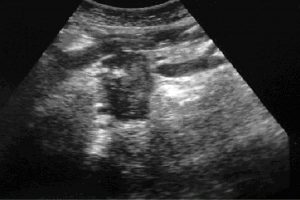

Diplomados en Ultrasonografía